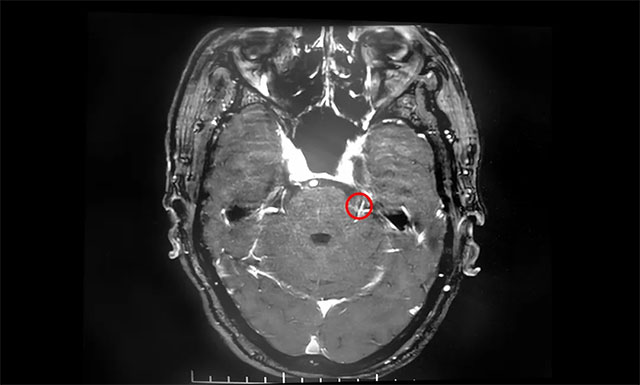

▲ 患者左側(cè)三叉神經(jīng)根部與小血管關(guān)系密切

在蔡司顯微鏡(雙熒光)下可見,患者左側(cè)三叉神經(jīng)后根外側(cè)有小靜脈與其位置較為緊密,并可見兩者間放置有墊片,考慮為前次微血管減壓手術(shù)放置的墊片。沈教授小心翼翼地游離三叉神經(jīng)根周圍蛛網(wǎng)膜,靈活操作手中纖細輕巧的顯微剪刀,剪斷約三分之一的三叉神經(jīng)后根……經(jīng)過近5個小時的手術(shù),患者生命體征平穩(wěn),安返監(jiān)護室。